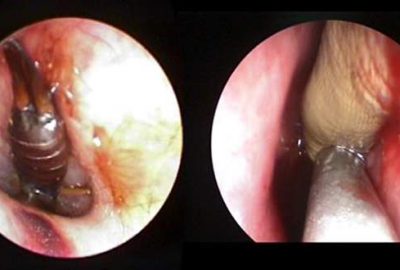

Burnundan ve kulağından öyle şeyler çıktı ki!